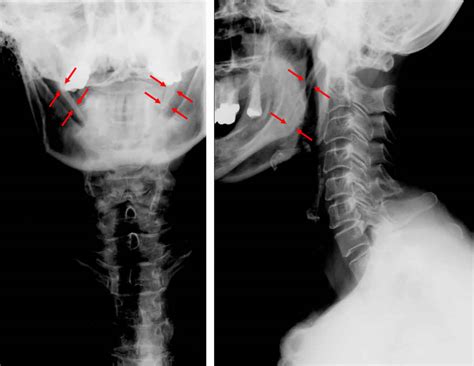

Diagnosing this condition requires more than just a physical examination of the throat. Because the root cause is structural, medical imaging is necessary to confirm the elongation of the styloid process or the calcification of the stylohyoid ligament.

• Computed Tomography (CT) Scan: This is the gold standard for diagnosis. A 3D CT scan of the neck clearly reveals the length, angulation, and thickness of the styloid process.